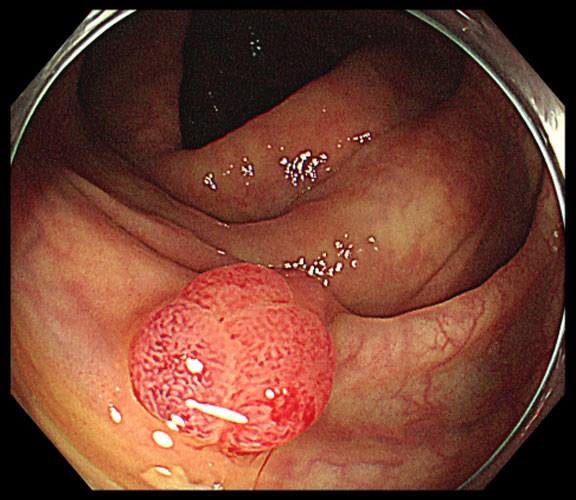

大腸ポリープとは、大腸の内側の粘膜にできる“いぼ”のようなもりあがった病変です。

特に「腺腫性ポリープ」は大腸がんの前がん病変として知られており、適切な内視鏡検査と切除によって大腸がんの予防が可能です。

大腸内視鏡検査

大腸内視鏡検査は、肛門から内視鏡を入れて、大腸の中を直接見て調べる検査です。

診断と治療が同時に可能で、最も信頼性の高い検査です。

大腸ポリープがあれば、その場で切除することも可能です。

平らなタイプや見つけにくい病変も発見でき、がんの予防に最も効果的です。